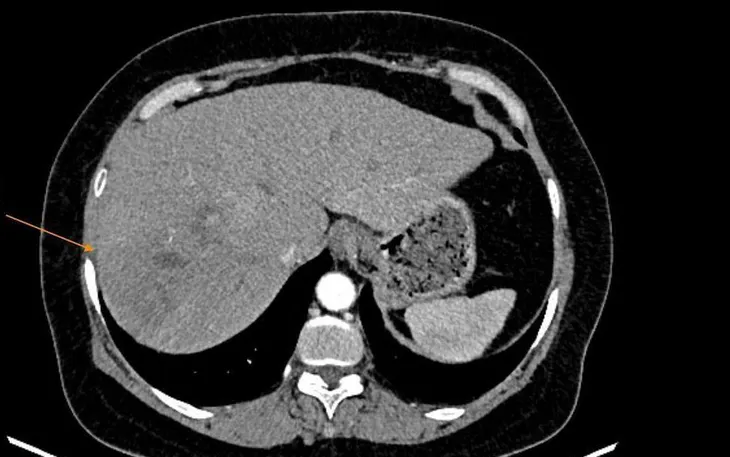

Bệnh nhân nhập viện trong tình trạng sốt rét từng cơn, nhiệt độ 39 độ C, kèm đau tức vùng hạ sườn phải. Dù đã tự dùng thuốc tại nhà nhưng tình trạng không cải thiện. Khi được thăm khám, kết quả xét nghiệm cho thấy bạch cầu ái toan tăng cao, Fasciola IgG dương tính. Siêu âm và CT phát hiện ổ áp xe ở gan phải, kích thước hơn 5 cm.